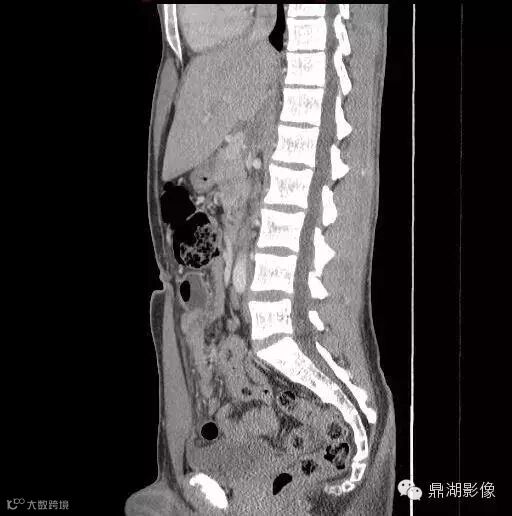

18岁男性,腹痛,定位模糊,无直肠出血。

影像学描述

诊断

Meckel憩室炎 Meckel's diverticulitis

典型的位置位于下腹部(少数盆腔内)中线附近(67%),尤其是肚脐附近是其典型位置,病变与肚脐关系密切尤其是可见纤维索相连高度提示为Meckel's 憩室炎。发生于回肠肠系膜对侧,距回盲瓣50-60cm以内。

肠系膜炎性改变常较显著,表现为系膜密度增高及周围脂肪内条索状影,部分可伴腹水。

憩室壁常增厚,增强后绝大多数可见粘膜面强化。